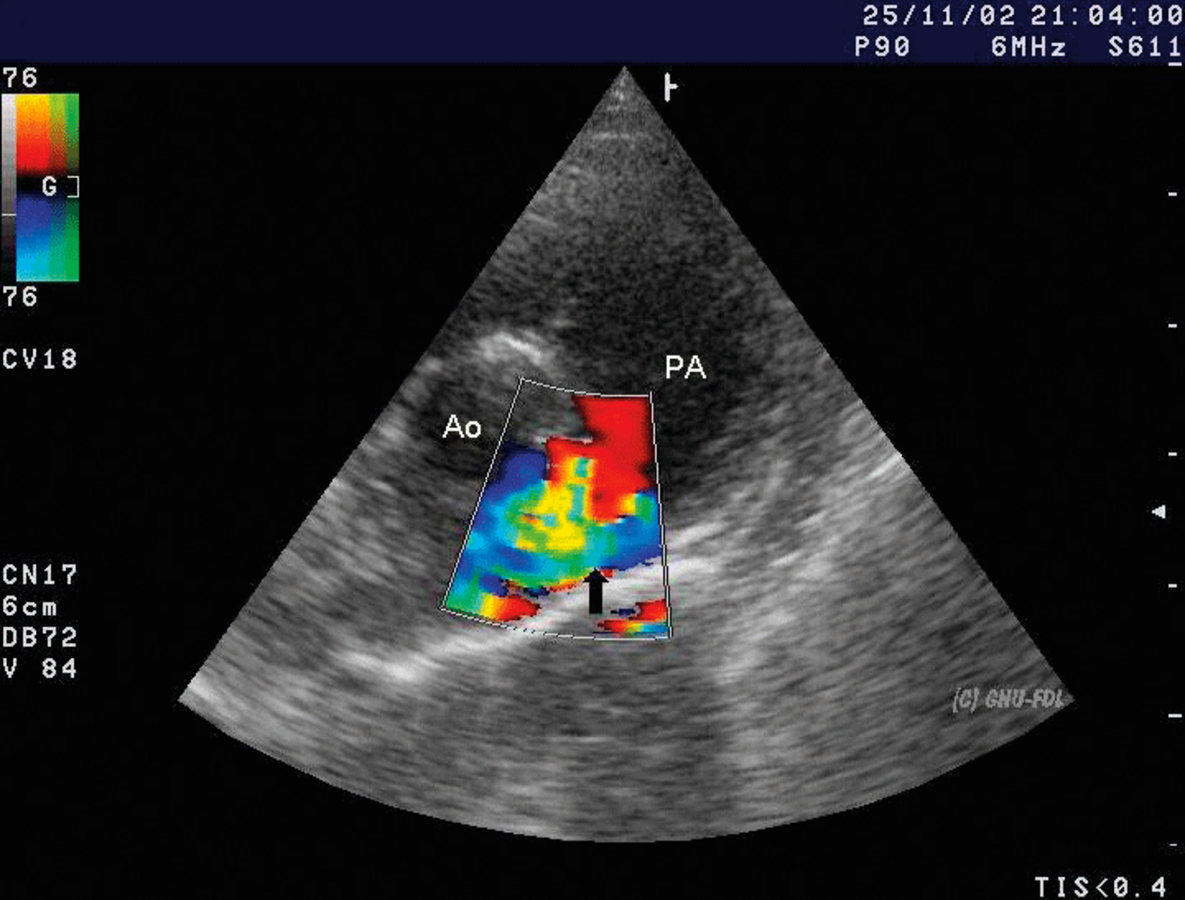

Kinder übergewichtiger Mütter haben häufiger einen persistierenden Ductus arteriosus.

In einer großen schwedischen Kohortenstudie beispielsweise fanden sich bereits ab einem BMI der Mutter von 25 kg/m2 bei den Kindern häufiger Vorhofseptumdefekte oder ein persistierender Ductus arteriosus überproportional häufig. Überschritt er 30 kg/m2 stellte man unter anderem vermehrt Aortenbogendefekte fest und der Nachwuchs von Frauen mit einem BMI von 35 kg/m2 oder mehr hatten ein erhöhtes Risiko für Transpositionen der großen Arterien. Die pathophysiologischen Zusammenhänge von der durch das Übergewicht der Mutter hervorgerufenen Störung und der Herzentwicklung in den einzelnen Embryonalstadien sind bisher noch nicht komplett verstanden. Allerdings geht man vom Zusammenspiel mehrerer Faktoren aus, so die Autoren.